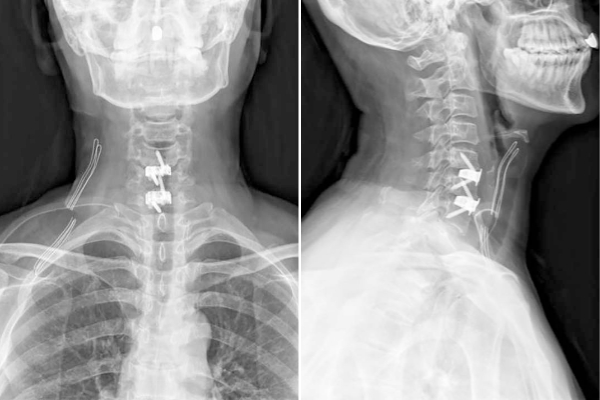

图1 单节段3D打印零切迹融合器置入术后影像

56岁的王先生因神经根型颈椎病长期饱受颈肩疼痛和右手拇指麻木的困扰,保守治疗无效后,接受了3D打印零切迹融合器手术。术后第一天,他的疼痛和麻木症状明显缓解,术后第三天便顺利出院。王先生表示:“手术效果立竿见影,恢复速度远超预期!”一周后,贺永雄团队又为一名两节段颈椎病患者成功实施手术(图2),术后患者颈肩痛和右前臂、手指麻木症状明显改善。

图2 双节段3D打印零切迹融合器置入术后影像